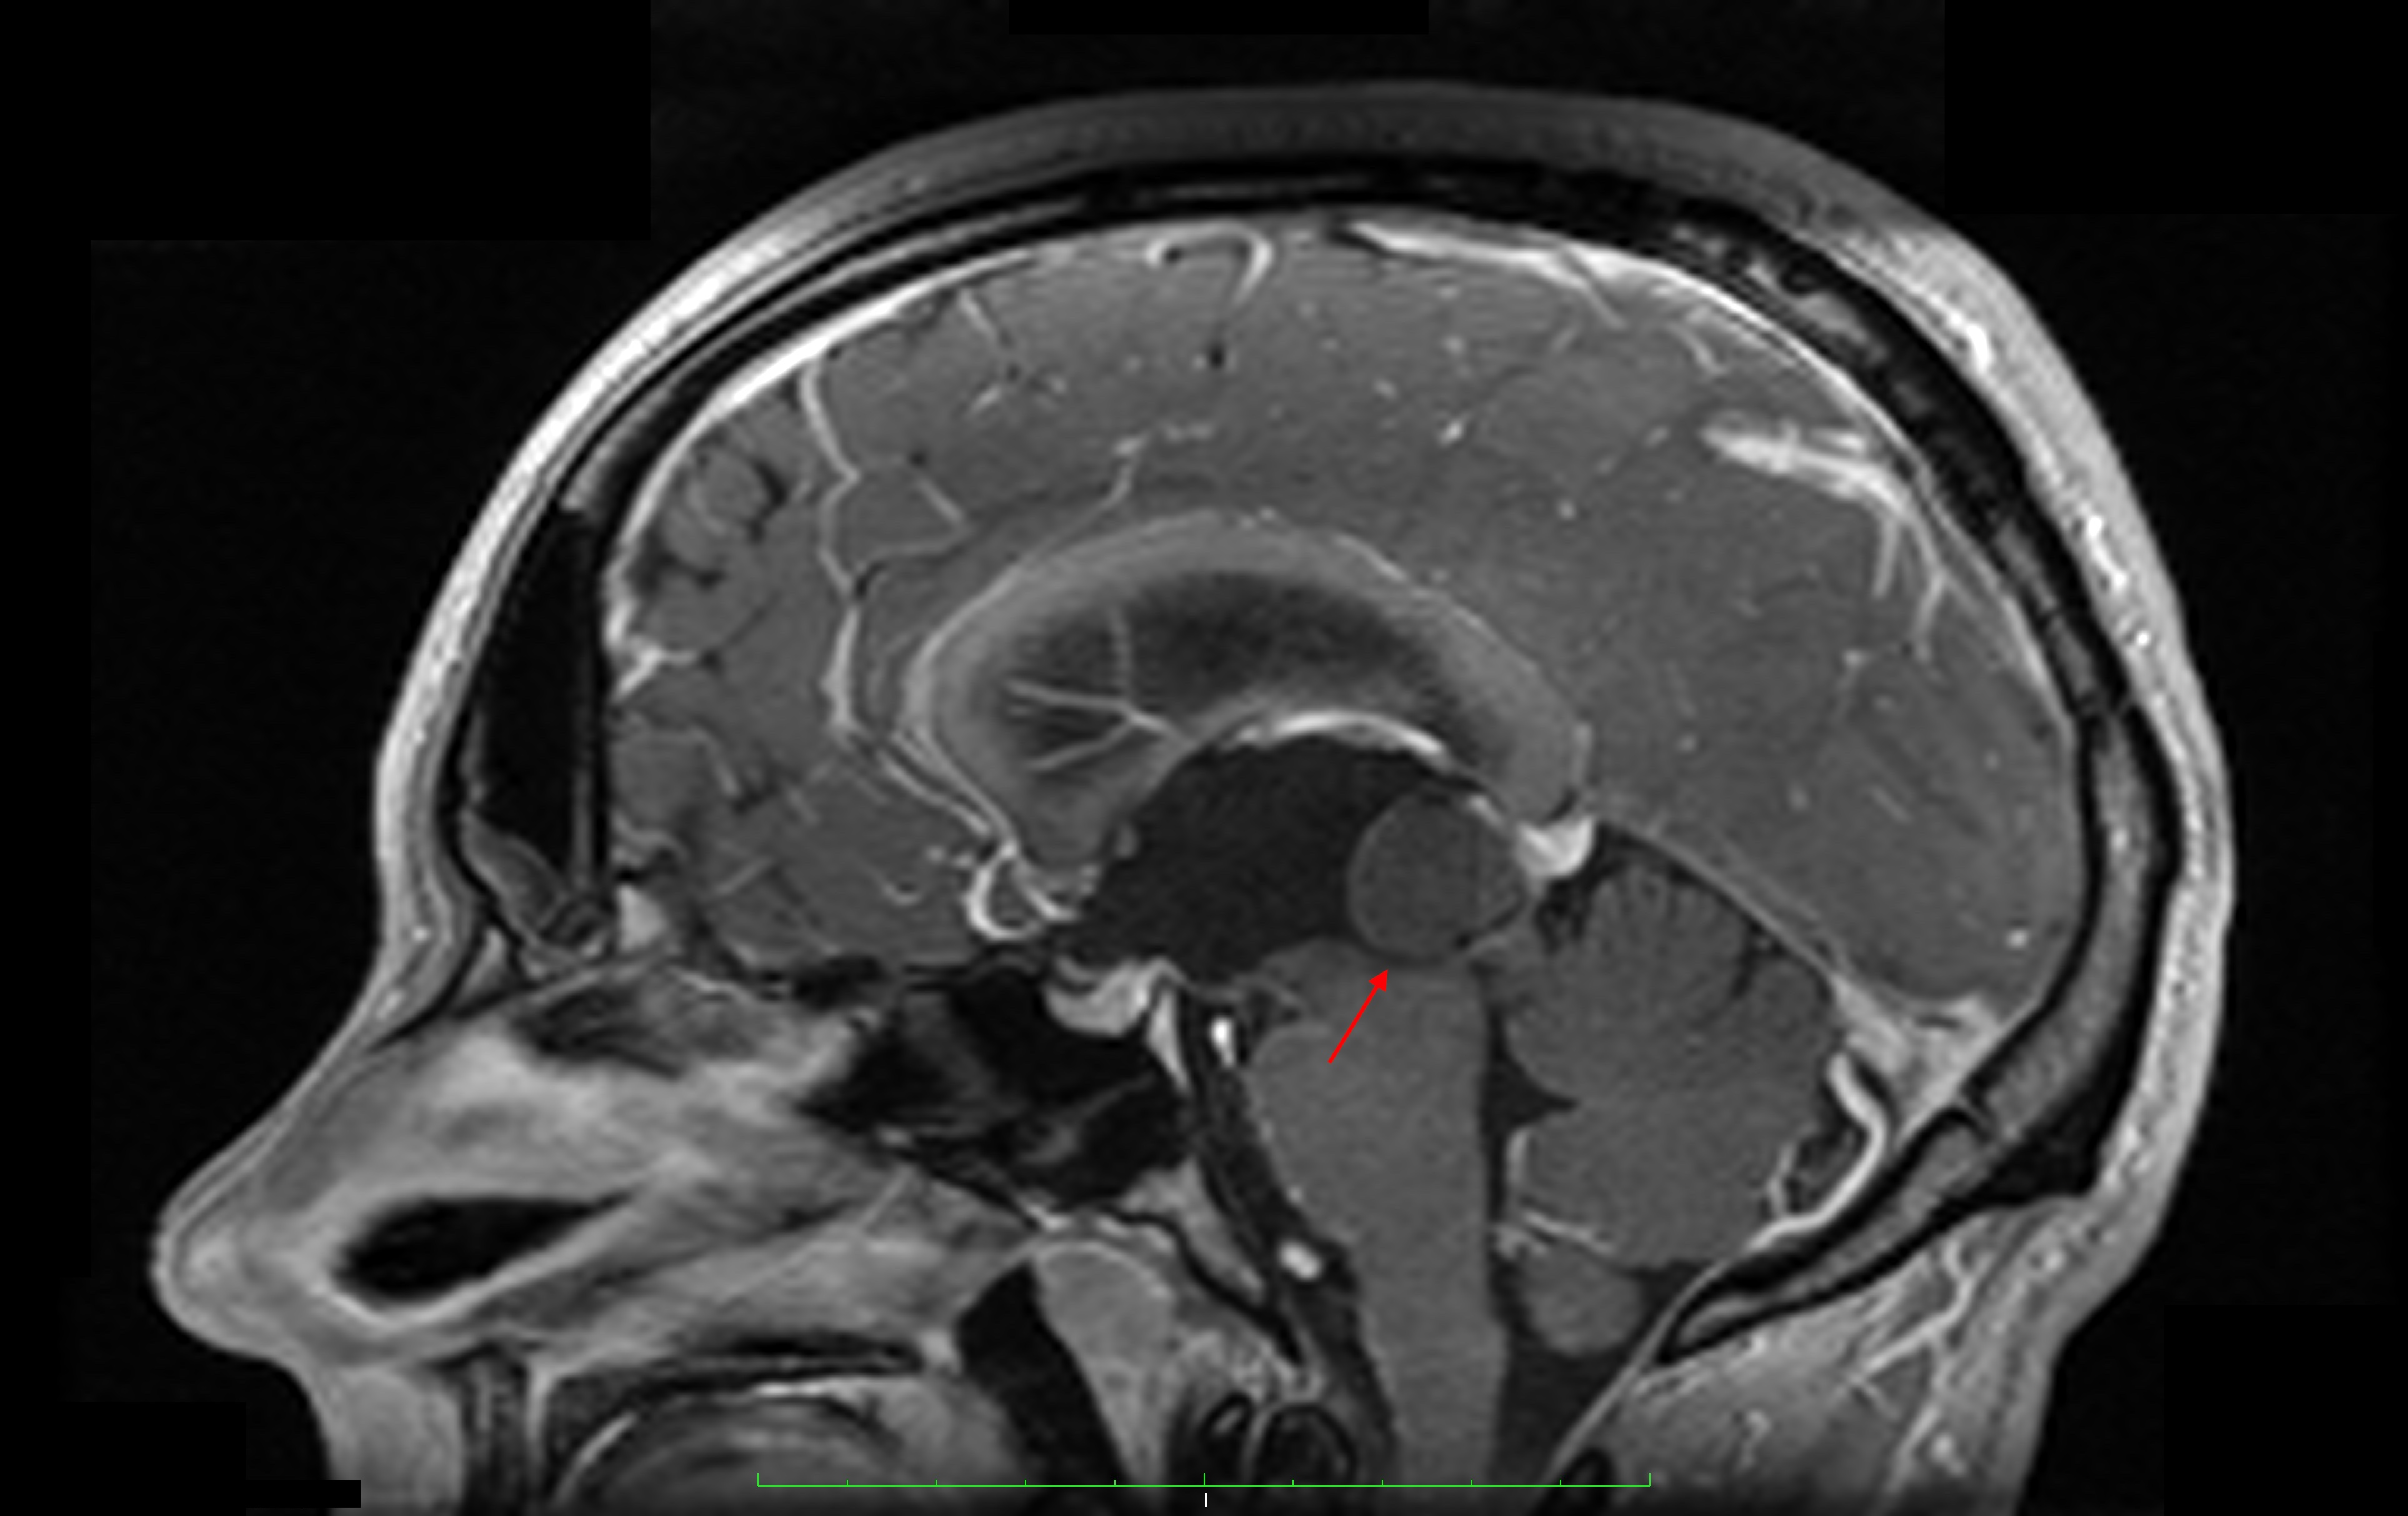

Pathologies of the pineal gland region are frequently encountered in daily neurosurgical practice. It is important to remember that, besides usually asymptomatic pineal gland cysts, neoplasms of a different origin may also occur in this region. The rarity of the most dangerous lesions – pineal gland apoplexy and pineal tumors – might cause problems with proper diagnosis and treatment. Their occurrence is commonly associated with symptomatic hydrocephalus caused by aqueductal stenosis. Currently, in such cases, endoscopic procedures, including endoscopic third ventriculostomy (ETV), are commonly and widely chosen as treatment options. Endoscopic procedures not only enable decompression of hydrocephalus but also further diagnosis of its cause. Herein, we present 3 case reports of endoscopic treatment with ETV performed in patients with hydrocephalus related to pineal region pathologies.